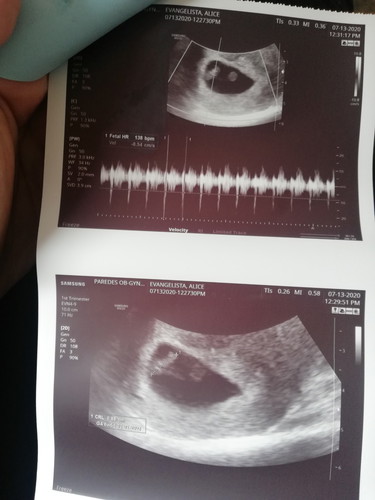

This is my scan last week, kasi bigla ako dinugo ng parang regla. Kaya sinugod ako sa hospital. Kinabukasan ayan sya, 138 bpm utz age is 6 weeks and 6 days. Niresetahan ako ng pampakapit. Until now may spotting ako minsan pinkish red pero madalas brown. Going to get a scan again tommorow after a week. ☺️ Sino relate sakin? Na maselan ang pagbubuntis.